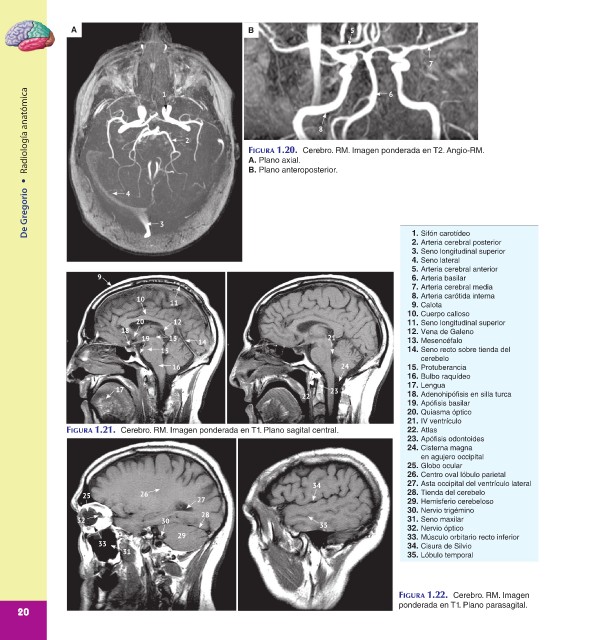

Radiología anatómica 2 FIGURA 1.20. Cerebro. RM. Imagen ponderada en T2. Angio-RM.

B. Plano anteroposterior.

• 4 A. Plano axial.

1. Sifón carotídeo

2. Arteria cerebral posterior

3. Seno longitudinal superior

4. Seno lateral

5. Arteria cerebral anterior

9 6. Arteria basilar

7. Arteria cerebral media

10 8. Arteria carótida interna

11 9. Calota

10. Cuerpo calloso

20 12 11. Seno longitudinal superior

18 12. Vena de Galeno

19 13 14 21 13. Mesencéfalo

15 14. Seno recto sobre tienda del

cerebelo

16 24 15. Protuberancia

16. Bulbo raquídeo

17. Lengua

17 23

22 18. Adenohipófisis en silla turca

19. Apófisis basilar

20. Quiasma óptico

21. IV ventrículo

FIGURA 1.21. Cerebro. RM. Imagen ponderada en T1. Plano sagital central. 22. Atlas

23. Apófisis odontoides

24. Cisterna magna

en agujero occipital

25. Globo ocular

26. Centro oval lóbulo parietal

34 27. Asta occipital del ventrículo lateral

25 26 27 28. Tienda del cerebelo

29. Hemisferio cerebeloso

30. Nervio trigémino

28

32 30 31. Seno maxilar

35 32. Nervio óptico

29 33. Músculo orbitario recto inferior

33 34. Cisura de Silvio

31 35. Lóbulo temporal

FIGURA 1.22. Cerebro. RM. Imagen

ponderada en T1. Plano parasagital.